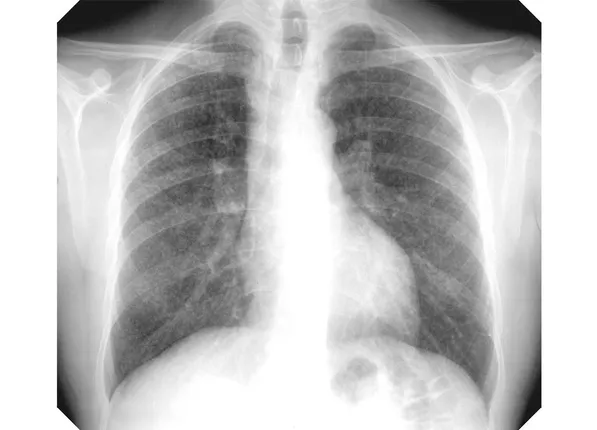

ସୁନ୍ଦରଗଡ଼: ଚିନ୍ତା ବଢ଼ାଉଛି ସିଲିକୋସିସ୍‌ ରୋଗ। ସୁନ୍ଦରଗଡ଼ ଜିଲ୍ଲାରେ କ୍ରମାଗତ ଭାବେ ରୋଗୀଙ୍କ ସଂଖ୍ୟା ଉଦ୍‌ବେଗଜନକ ଭାବେ ବୃଦ୍ଧି ପାଉଥିବାବେଳେ ଏହାର ଚିକିତ୍ସା ହୋଇନପାରିବା ଚିନ୍ତାର କାରଣ ହୋଇଛି। ରାଉରକେଲା ପୁରୁଣା ଜଲଦାର ଅଜୟ ଗିରି ଏକ ପଥର କ୍ରସର୍‌ରେ ୨୩ ବର୍ଷ ଧରି କାମ କରୁଥିଲେ। ଫୁସ୍‌ଫୁସ୍‌ଜନିତ ରୋଗରେ ଆକ୍ରାନ୍ତ ଅଜୟ ବୁର୍ଲା ବୀର ସୁରେନ୍ଦ୍ରସାଏ ଡାକ୍ତରଖାନାରେ ପରୀକ୍ଷା କରାଇବା ପରେ ତାଙ୍କୁ ସିଲିକୋସିସ୍‌ ରୋଗ ହୋଇଥିବା ଜଣାପଡ଼ିଥିଲା। ସିଲିକୋସିସ୍‌ ରୋଗର ଚିକିତ୍ସା ନଥିବା କହି ତାଙ୍କୁ କେବଳ ଫୁସ୍‌ଫୁସ୍‌ ରୋଗର ଚିକିତ୍ସା କରି ଘରକୁ ପଠାଇ ଦିଆଗଲା। ଖଣି ଅଞ୍ଚଳରୁ ଉତ୍ପନ୍ନ ମାରାତ୍ମକ ସିଲିକୋସିସ୍‌ ରୋଗ ଯକ୍ଷ୍ମା ଓ ଆଜମା ଭିତରେ ଲୁଚି ଯାଉଛି। ଏହି ରୋଗ ସମ୍ପର୍କରେ ସ୍ବାସ୍ଥ୍ୟ ବିଭାଗର କୌଣସି ଅଧ୍ୟୟନ ନାହିଁ। ସଚେତନତା ଅଭାବରୁ ଏ ରୋଗ ଦିନକୁ ଦିନ ବଢ଼ିଚାଲିଛି।

ସିଲିକୋସିସ୍‌ ସଂକ୍ରାନ୍ତରେ ଖଣିବହୁଳ ସୁନ୍ଦରଗଡ଼ ଜିଲ୍ଲାରୁ ଚମକାଇ ଦେଲା ଭଳି ତଥ୍ୟ ସାମନାକୁ ଆସିଛି। ୨୦୧୫ରୁ ୨୦୧୯, ୫ ବର୍ଷ ମଧ୍ୟରେ ଜିଲ୍ଲାରେ ଏହି ରୋଗରେ ଆକ୍ରାନ୍ତଙ୍କ ସଂଖ୍ୟା ୭୨୬୯୫ ଥିବା ସ୍ବାସ୍ଥ୍ୟ ବିଭାଗର ରିପୋର୍ଟ କହୁଛି। ତଥ୍ୟାନୁସାରେ, ୨୦୧୫ରେ ବର୍ହିବିଭାଗରେ ୧୦୯୯୭, ୨୦୧୬ରେ ୧୩୧୨୪, ୨୦୧୭ରେ ୧୭୦୮୪, ୨୦୧୮ରେ ୨୦୭୫୦, ୨୦୧୯ରେ ୧୦୭୪୦ ସିଲିକୋସିସ୍‌ ଲକ୍ଷଣ ଥିବା ରୋଗୀ ଆସିଥିଲେ। ସେହିପରି ଜିଲ୍ଲାର ଡାକ୍ତରଖାନାଗୁଡ଼ିକରେ ୫ ବର୍ଷରେ ୨୬୩ ଜଣ ରୋଗୀ ଚିକିତ୍ସିତ ହୋଇଥିବା ତଥ୍ୟ ରହିଛି। ୨୦୧୫ରେ ୨୯, ୨୦୧୬ରେ ୩୯, ୨୦୧୭ରେ ୧୨୨,  ୨୦୧୮ରେ ୬୩ ଓ ୨୦୧୯ରେ ୧୦ ଜଣ ରୋଗୀ ଚିକିତ୍ସିତ ହୋଇଥିଲେ। ତେବେ ଆଶ୍ଚର୍ଯ୍ୟଜନକ ଭାବେ ତା’ ପରବର୍ଷ ଅର୍ଥାତ୍‌ ୨୦୨୦ ରିପୋର୍ଟରେ ରୋଗୀ ସଂଖ୍ୟା ଶୂନ ରହିଛି। ସିଲିକା ନାମକ ଏକ ଗୁଣ୍ଡ ଯୋଗୁ ହେଉଥିବା ସିଲିକୋସିସ୍‌ ରୋଗ ଫୁସଫୁସକୁ ଆକ୍ରାନ୍ତ କରିଥାଏ। ବିଶେଷ କରି ପଥର, ସୁନାଖଣି, ଚୂନପଥର, କାଚ, କୋଇଲା ଖଣି ସମେତ ସିମେଣ୍ଟ କାରଖାନାର ଶ୍ରମିକମାନେ ଏଥିରେ ଆକ୍ରାନ୍ତ ହୋଇଥାନ୍ତି। ସୁନ୍ଦରଗଡ଼ରେ ଉପରୋକ୍ତ ଖଣି କାରଖାନା ରହିଥିବାରୁ ସିଲିକୋସିସ୍‌ ଆକ୍ରାନ୍ତଙ୍କ ସଂଖ୍ୟା ଏଠାରେ ଅଧିକ। କିନ୍ତୁ ସ୍ବାସ୍ଥ୍ୟ ବିଭାଗ ଏହାକୁ ସେତେଟା ଗୁରୁତ୍ବ ଦେଉ ନଥିବା ଅଭିଯୋଗ ହେଉଛି। ଜିଲ୍ଲା ମୁଖ୍ୟ ଚିକିତ୍ସା ଓ ଜନସ୍ବାସ୍ଥ୍ୟ ଅଧିକାରୀ ଡ. ସୁରେଶଚନ୍ଦ୍ର ମହାନ୍ତି କହିଛନ୍ତି ସିଲିକୋସିସ୍‌ ରୋଗ ଚିହ୍ନଟ ବା ଚିକିତ୍ସା ବ୍ୟବସ୍ଥା ନଥିବାରୁ ଏ ସମ୍ପର୍କରେ ଜାଣିବା ମୁସ୍କିଲ।